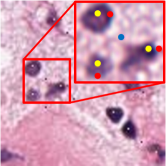

III-E Impact of the Perturbation in Point Annotation

In clinical practice, due to the time constraint, pathologists cannot exactly put the annotation point at the center of a nucleus. We carry out experiments to investigate the impact of point perturbation to segmentation performance. To simulate the actual annotations, we perform a uniform random shift within different ranges of the generated point annotations. Several examples are shown in Fig. 5 illustrating that the small shift makes the points not too far from the center, but there are still some cases that the points are close to the boundary or even outside the nuclei. The number of points falling outside of the nuclei increases as the shift increases. Fig. 6(a) gives a quantitative illustration that as the shift increases from 0 to 20 pixels, the ratio of point annotations being within the nuclei decreases from 98.66% to 39.54%. Obviously, the offset of the points reduces the quality of the coarse labels, especially the accuracy of the nuclei in cluster labels is reduced from 85.46% to 49.72%. We train the models with the point annotations obtained by different shifts and calculate two object-level metrics. As illustrated by the changing trends of and AJI versus the shifts in Fig. 6(b), the segmentation accuracy of the proposed method degrades more gradually than that of the cluster results. The four-pixel shift only result in 1.38% drop in and 1.15% drop in AJI to the segmentation results of the proposed method, but 2.75% drop in and 3.27% drop in AJI to the cluster results. Even though the eight-pixel shift makes about one fifth point annotations not in the nuclei, the segmentation performance can still reach 70.75% in and 50.72% in AJI, respectively, which verifies the robustness of our method to point annotation offset. We believe that the robustness owes to the label propagation which refines the coarse labels to compensate for the impact of the offset. In clinical practice, professional pathologists will ensure the quality of point annotations, thus avoiding performance degradation caused by excessive offset. Some nuclei instance segmentation results with different shifts of point annotation are presented in Fig. 8. The robust instance segmentation performance lays the foundation for further counting and morphological feature extraction of nuclei on pathology images.